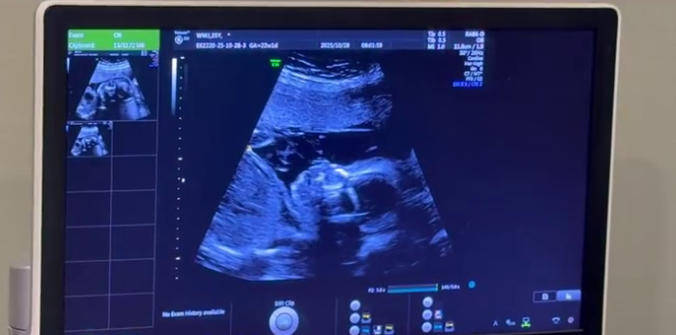

首先,从23周的8mm到28周的18mm,这不仅仅是数字的增长,更是一个重要的临床信号。

8mm(23周):处于“肠管充液”的临界值或轻度扩张范围,有生理性(如胎儿吞咽羊水后一过性增多)或轻度异常可能,需要密切观察。

18mm(28周):这已明确属于病理性肠管扩张。根据国内外胎儿医学指南,肠管直径≥15mm时,提示存在机械性肠梗阻或其他严重问题的可能性显著增高。